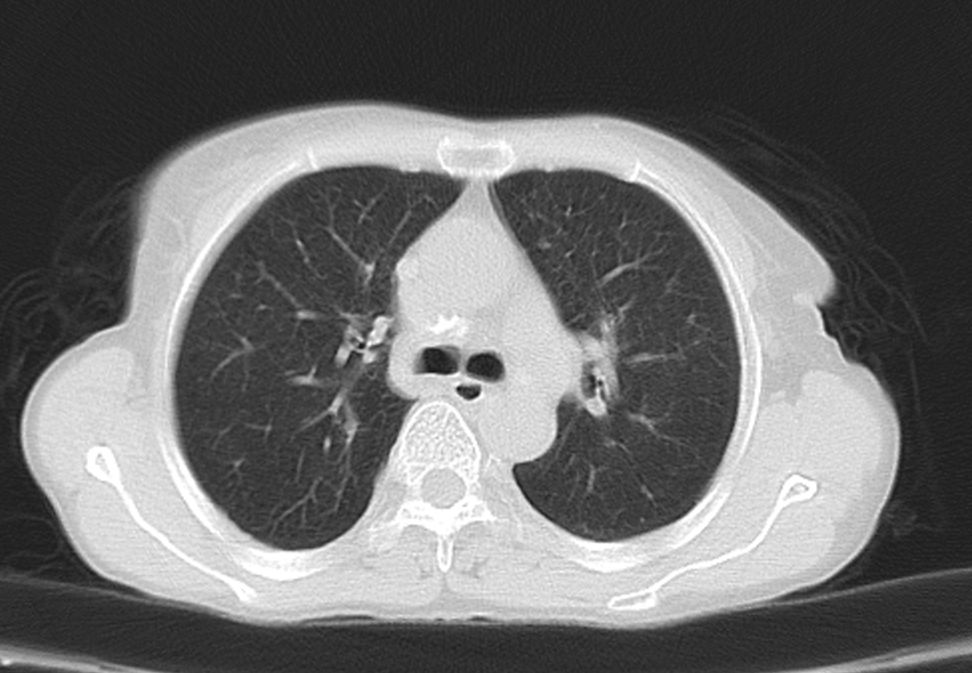

标题: CT21609:右乳包块1年,请各位讨论分析一下,乳腺CA, [打印本页]

标题: CT21609:右乳包块1年,请各位讨论分析一下,乳腺CA,

考虑---右乳癌并胸壁、肋骨、双肺转移。

考虑乳腺癌侵犯肋骨、胸壁及两肺转移可能性大。

右乳癌并胸壁、肋骨、双肺转移。

考虑右侧乳腺癌侵犯肋骨、胸壁及两肺转移。

支持考虑---右乳癌并胸壁、肋骨、双肺转移。

考虑右侧乳腺癌侵犯肋骨、胸壁及两肺转移可能。

考虑右侧乳癌并胸壁、肋骨及双肺多发性转移。